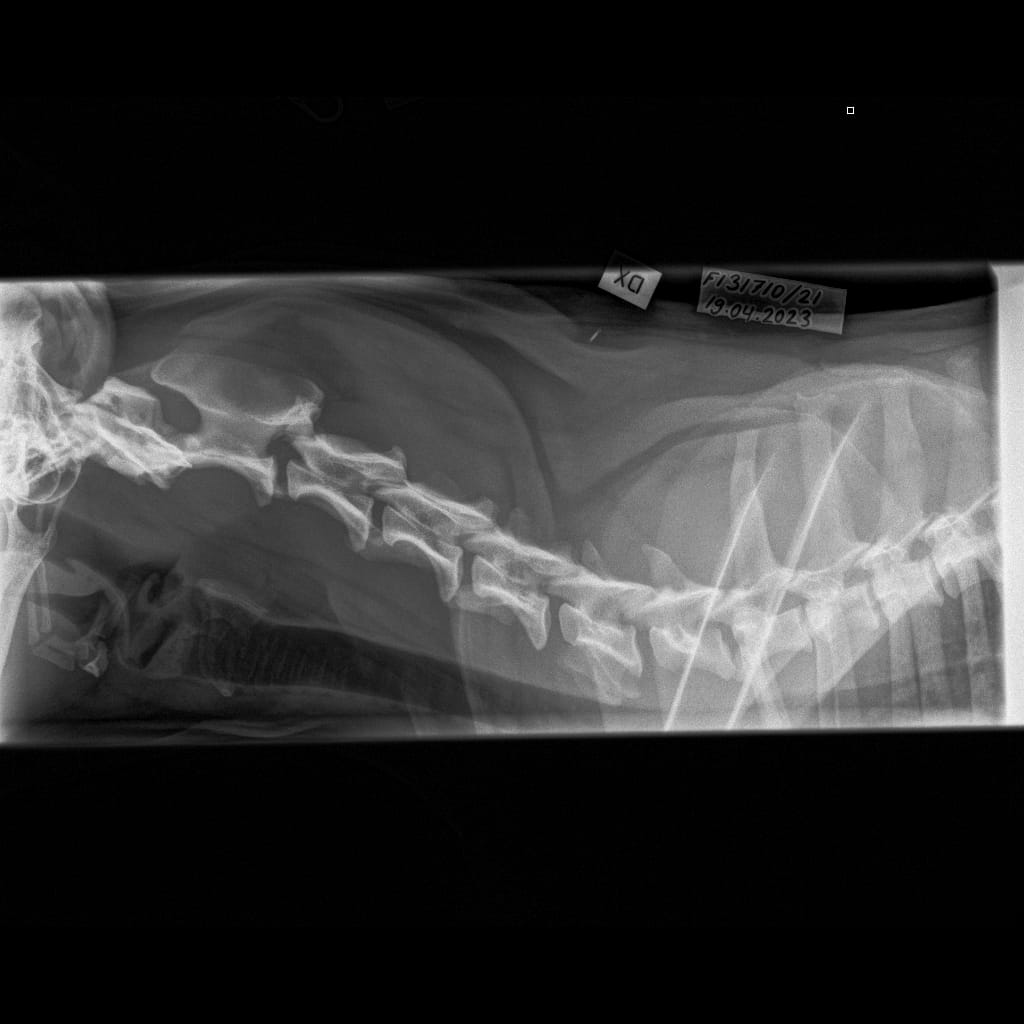

Selkäranka -Kaularanka LAT-6.11.2023-16_02_20-906 (1)